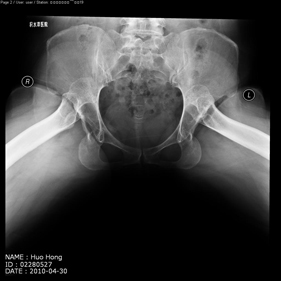

shortening osteotomy and total hip replacement for bilateral severe dysplasia of hip with high riding